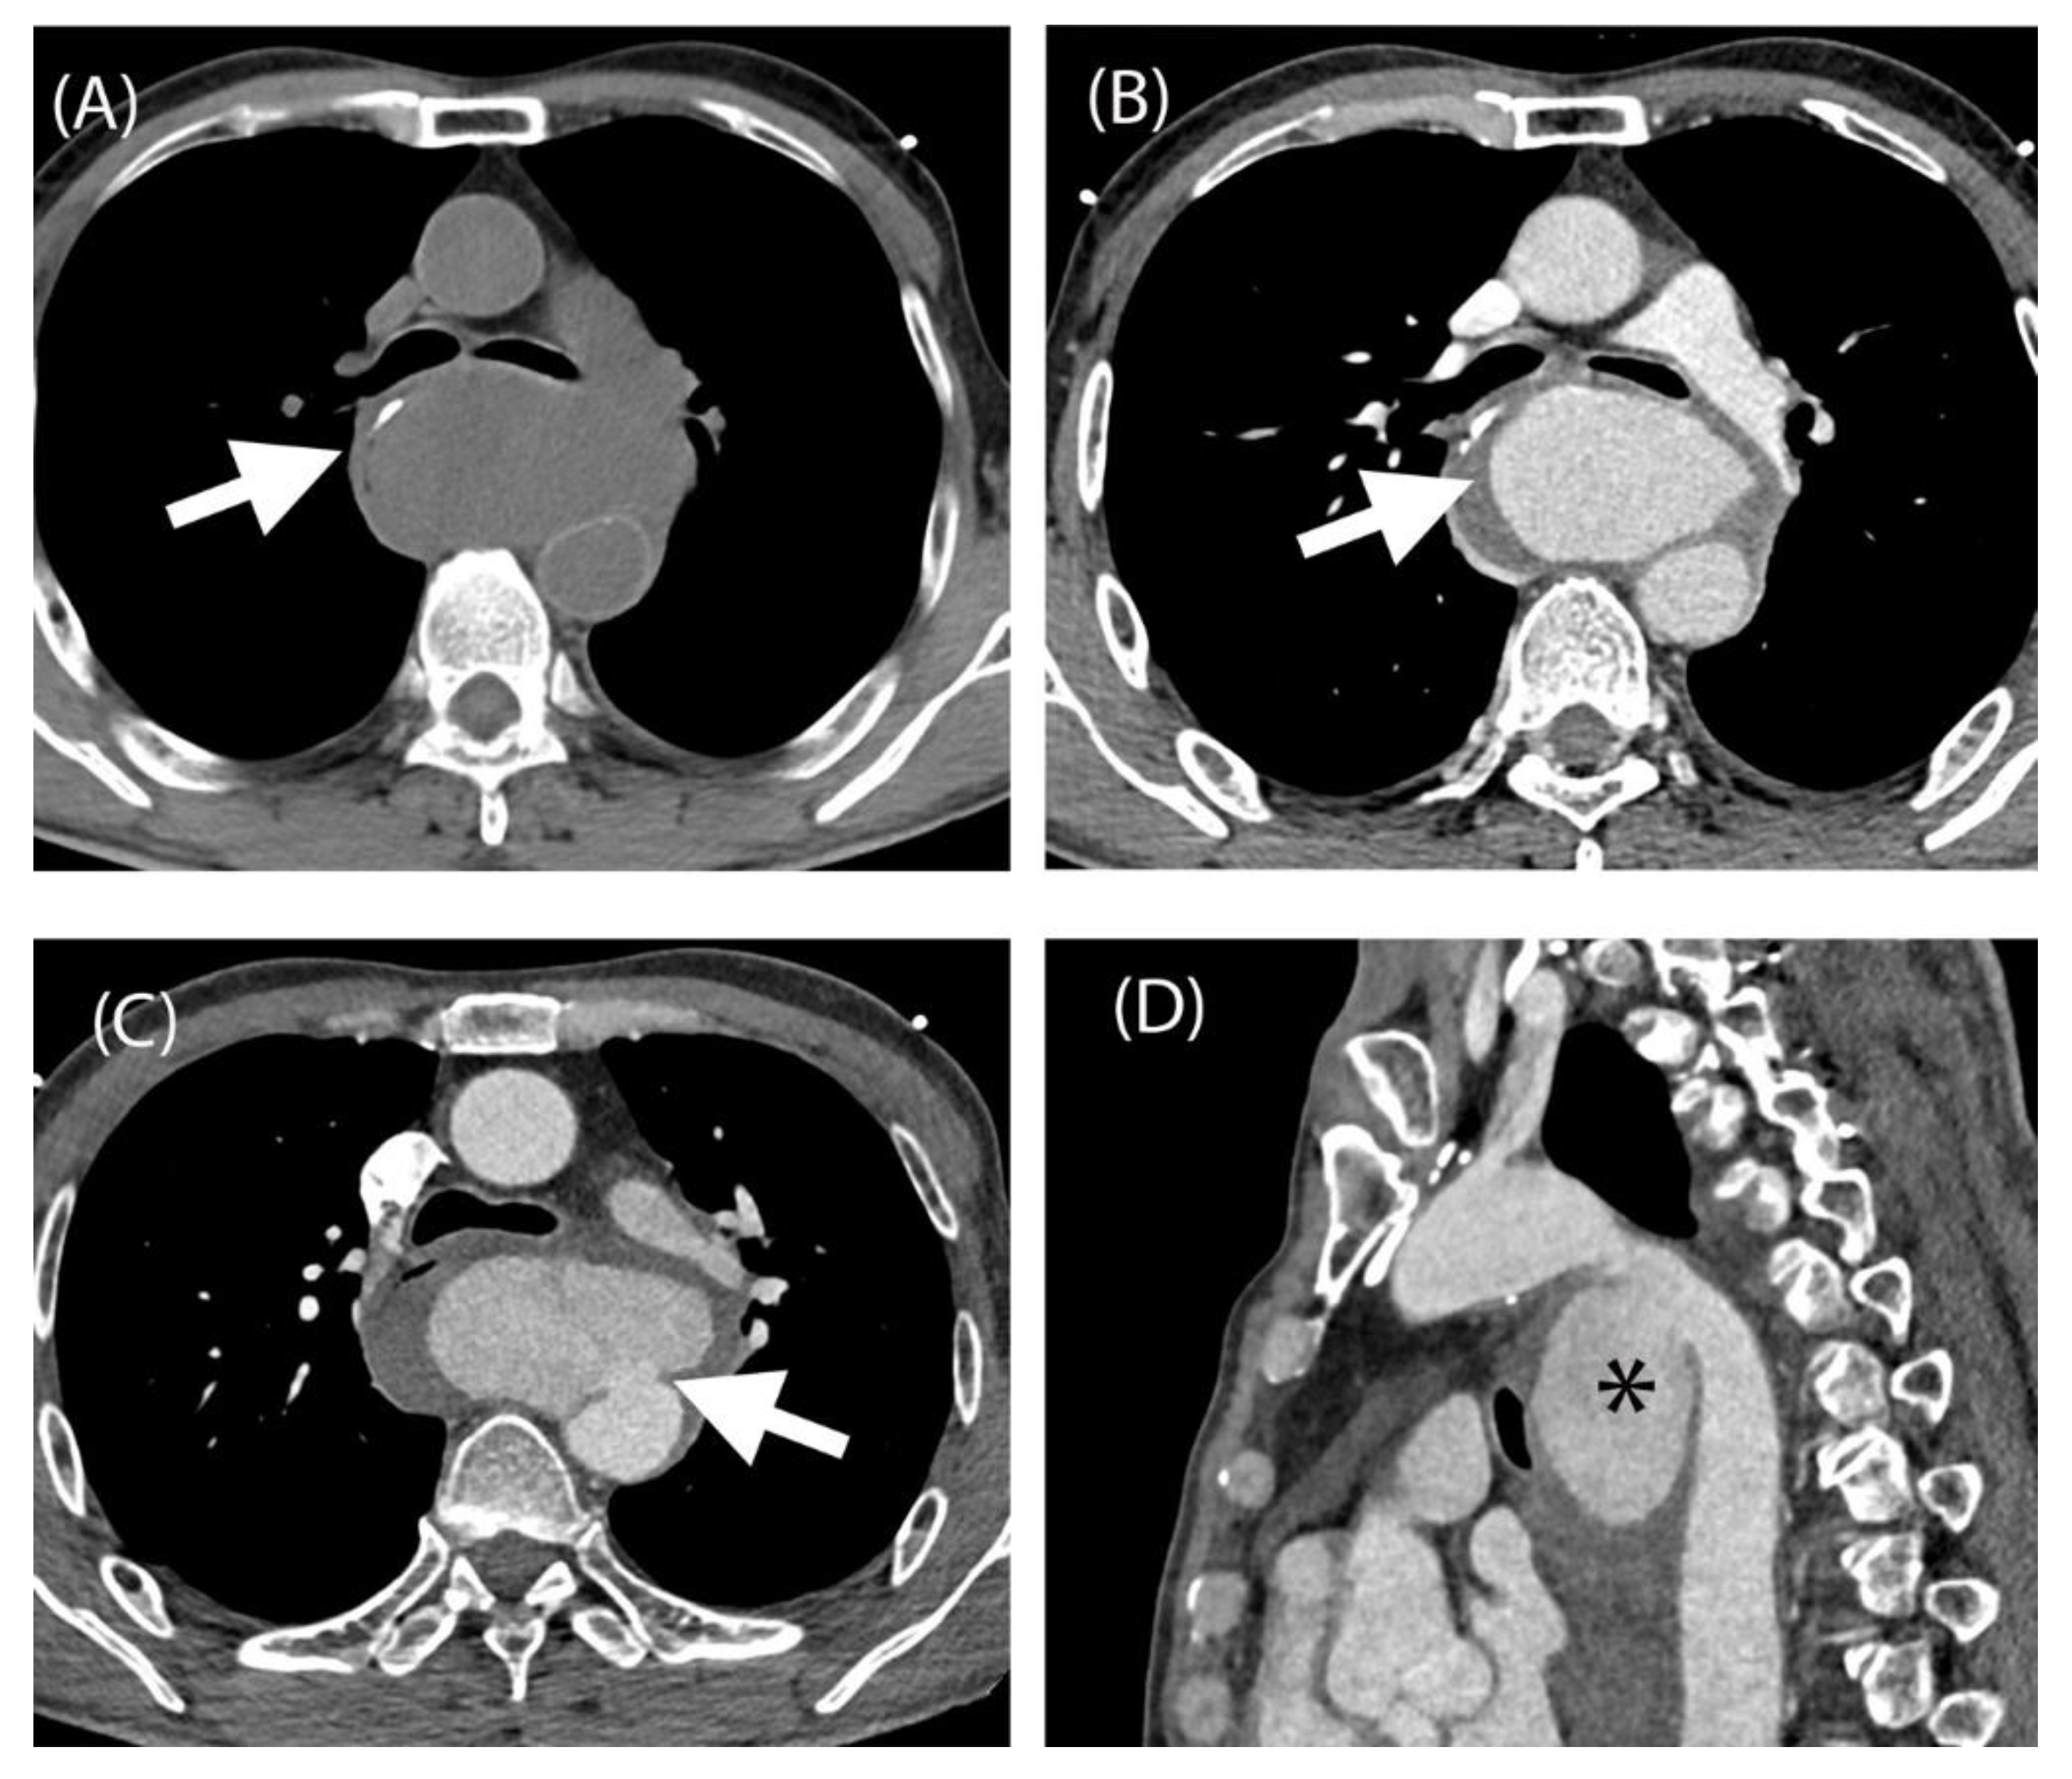

Figure 1. Complication of ingestion fish bone complicated with aortic pseudoaneurysm. Unenhanced CTA aorta at the level of carina showing hyperdense linear structure suggestive of fish bone within the oesophageal wall (A, white arrow). Contrasted study of CTA aorta of the same level at the carina showing contrast within the pseudoaneurysm sac and surrounding haematoma (B, white arrow). CTA aorta at the level of carina showing the neck of pseudoaneurysm exerting mass effect causing displacement of carina anteriorly and oesophagus right laterally (C, white arrow). The oesophagus at this level is compressed by the pseudoaneurysm causing obstruction and failure of nasogastric tube insertion. Sagittal reformatted image of CTA aorta exhibiting the pseudoaneurysm (D, asterisk). A, unenhanced CTA aorta. B-C, arterial phase of CTA aorta. D, sagittal view of CTA aorta. Note: CTA: Computed Tomography Angiography. Common causes of thoracic pseudoaneurysm are atherosclerosis, postoperative sequela, trauma, infection and iatrogenic. Accidental fish bone ingestion is commonly encountered and is usually located to the oropharynx and can be managed by otorhinolaryngology (ORL) team via scope. However, a fish bone is able to migrate distally in the oesophagus, and thoracic oesophagus was reported to be the second most common location after cervical oesophagus [1]. Our patient had fish bone in his thoracic oesophagus which led to the injury to the adjacent aorta. Although rare, the formation of aorto-oesophageal fistula may lead to aortic pseudoaneurysm. It is usually caused by direct penetration of foreign body or infection of the oesophageal wall leading to the rupture [2]. Symptoms of penetrating fish bone injury complicated with aortic pseudoaneurysm are non-specific. Our patient presented with chronic chest pain and recurrent hospital visits. It was mistaken as pneumonia and low-risk chest pain as he was discharged a few times with planned treatment. Detailed history taking elicited neglected fish bone ingestion and presence of a mass from echocardiogram led to the CTA thoracic aorta, which localised the fish bone in the thoracic oesophagus and confirmation of its complication which was pseudoaneurysm. Treatment of thoracic pseudoaneurysm includes surgical intervention, video-assisted thoracic surgery (VATS) [3] or endovascular graft [1]. Surgical intervention is a more effective, albeit an invasive procedure, to avoid eruption of a pseudoaneurysm. However it can be debilitating to patient as it can cause traumatic injury and has a relatively high mortality rate [1]. Lung abscess is one of the complications of fish bone ingestion which can be managed by VATS. Endovascular repair is a less invasive option to treat aortic pseudoaneurysm and suitable for high-risk patients. It can effectively control the bleeding and place the patient temporarily out of danger if there are associated complications [2]. In comparison to open repair, endovascular repair has advantages in terms of quick recovery, few complications and low mortality [4]. Oesophageal repair is usually done for oesophageal perforation. Factors affecting the type of operation, whether direct repair or partial resection of the oesophagus depend on the location of perforation, the type of foreign body and the degree of mediastinitis [5]. Mediastinal infection due to foreign body may also invade to the aortic wall leading to myocytic aneurysm. Open repair is the gold standard of treatment for mycotic aneurysm but this requires high technical conditions. This includes aggressive debridement of the infection, prosthetic reconstruction as well as lifelong antibiotics treatment [2].